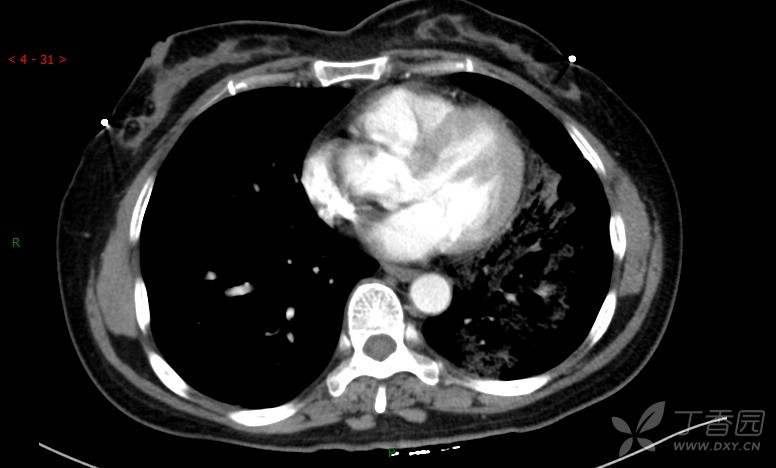

腺泡结节影,蜂窝征,这些都在提示……(病例3连发,附其他2例链接,病理已公布)

原帖名:胸部典型病例3(病例3连发,附其他2例链接)

咳嗽1年余,加重7天。

患者于1年余前始受凉后出现咳嗽,多为干咳,未在意,未到医院就诊。近3月患者出现咳痰,多为黄色粘痰,量大,伴乏力,偶有头晕、心慌,无发热、胸痛、憋喘,无低热、盗汗、咯血、胸痛,无头痛,无恶心、呕吐、腹痛、腹泻,无尿频、尿急、尿痛,在当地诊所给予抗感染等对症支持治疗(具体药物及剂量不详),症状仍时有反复。患者于1月余前到外院就诊,行胸部CT提示双肺炎症,左肺重,考虑为“间质性肺炎”,给予“左氧氟沙星、利巴韦林、头孢哌酮舒巴坦钠注射液”治疗,复查胸部CT示病灶吸收不理想,后出院继续于诊所对症治疗(具体药物及剂量不详),效果欠佳。7天前患者无明显诱因出现上述症状加重,为求进一步诊治,特来我院就诊,我院门诊以“肺炎(重症)?”收入留观室,留观室给予“盐酸莫西沙星氯化钠”等对症治疗后,今日转入我科。患者自发病以来,神志清,精神差,饮食正常,睡眠增多,大小便正常,体重近3月减轻5公斤余。